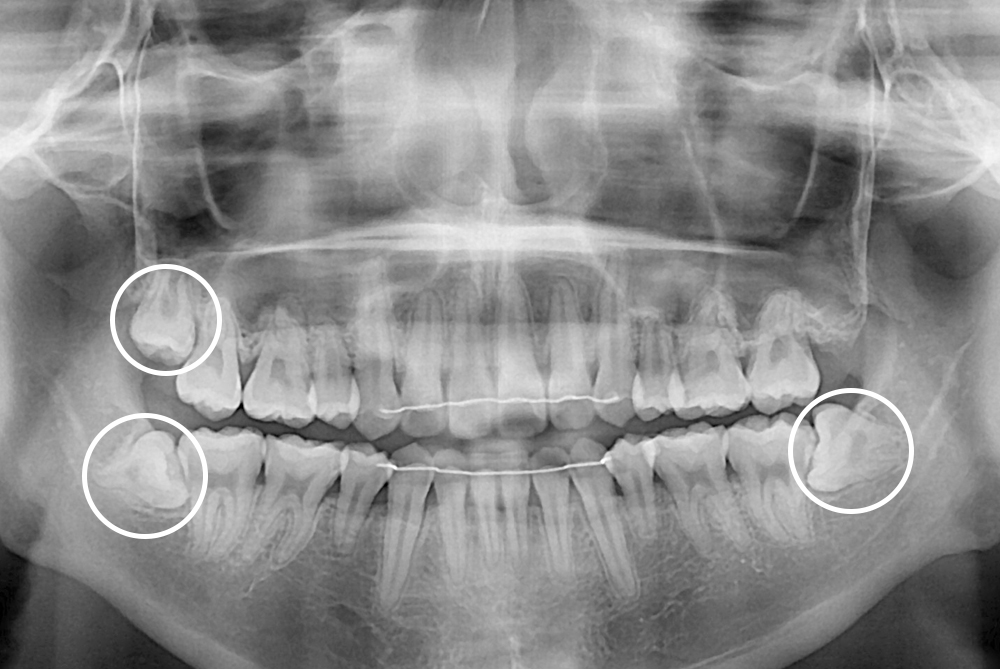

[사랑니] 매복 사랑니 발치

치료후 : 2017-06-01

세종치과는 구강악안면외과학 박사이신 원장님이 발치하는 치과입니다.